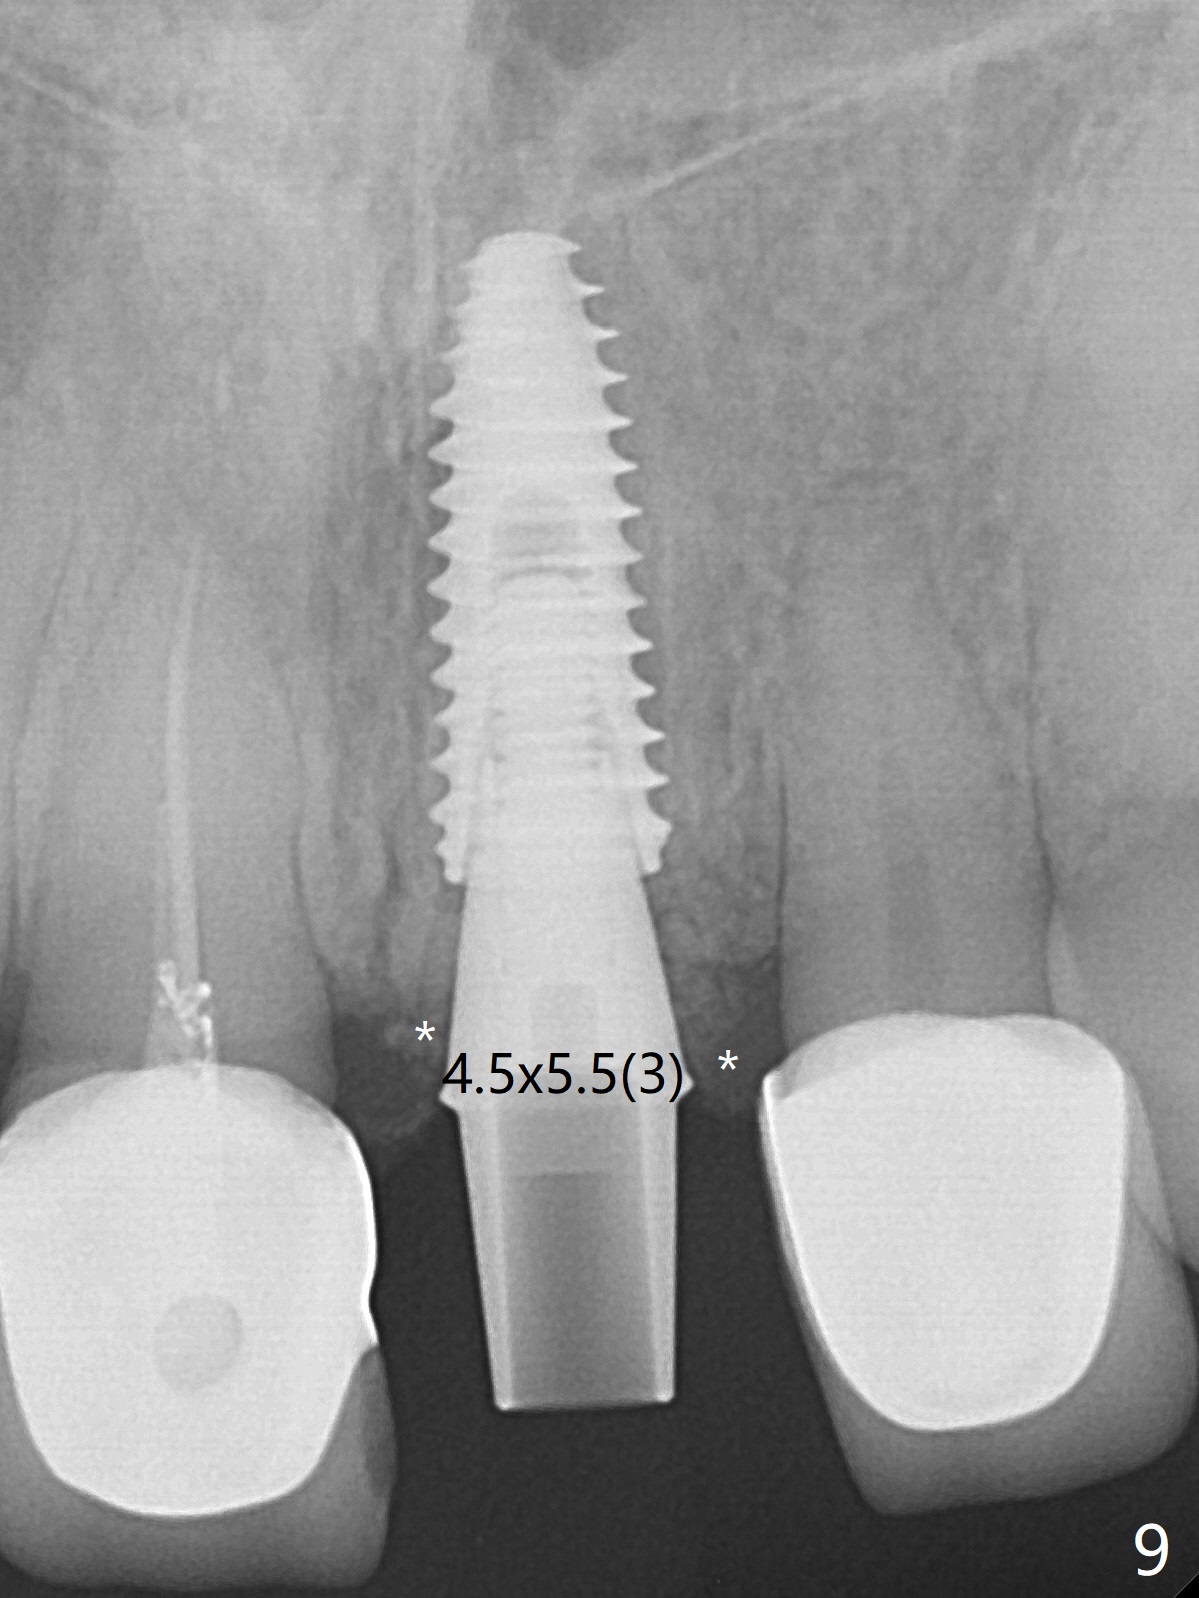

After sectioning the splinted crowns at #8 and 9 (Fig.1,2 (*: open bite)), the tooth #9 is deemed nonsalvageable because of caries and the crown/retainer of #8 is recemented. The trajectory of initial osteotomy is off (Fig.3 (red line: ideal trajectory)). Using Lindamann bur twice does not improve the trajectory (Fig.4,5). It appears that a new osteotomy should be established in the distal wall of the socket (Fig.5 red line (initial entry point and angle), Fig.6). Following sequential osteotomy, a 4x10 mm dummy implant is placed with stability and ~ 3.5 mm apical space (Fig.7 red line). A final implant (4x11.5 mm) is placed subcrestal (except buccal, Fig.8). With further placement of the implant, a 4.5x5.5(3) mm abutment and Vera graft are placed (Fig.9) prior to fabrication of an immediate provisional. In all, a new osteotomy site should be set up when the trajectory is to be changed substantially. There is no gross bone loss 4.5 months postop (Fig.10). There is shade mismatch when a porcelain-fused-Zirconia crown is tried in (Fig.11, as compared to Fig.1). The latter is corrected when a PFM crown is cemented (Fig.12).